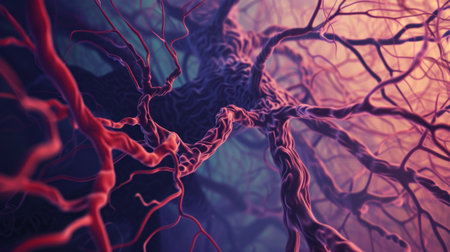

Macro view of human blood vessel network with red and blue tones showing capillaries and vein structure, ideal for illustrating medical anatomy and biology research.

Vessel flow texture in red and blue lighting showing microscopic circulation system pattern symbolizing human biology, anatomy, and healthcare science visualization.